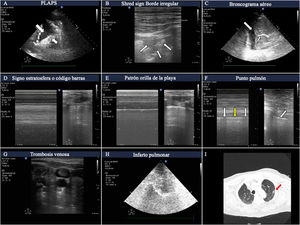

Hallazgos más frecuentes en pacientes con insuficiencia respiratoria aguda. A)Imágenes de PLAPS mostrando zonas hiperecoicas que delimitan un borde mal definido (flecha pequeña) y derrame pleural (flecha grande). B)Consolidación subpleural consistente en zona hipoecoica en contacto con la línea pleura, rodeada de borde hiperecoico irregular (shred sign). C)Imagen de broncograma aéreo mostrando líneas hiperecoicas (flecha pequeña) en el seno de un pulmón hepatizado rodeado de derrame pleural adyacente (flecha grande). D)Patrón en «código de barras», también denominado «de la estratosfera» en el modoM, correspondiente a un neumotórax. E)Patrón de «orilla de la playa» de un pulmón con un deslizamiento pleural preservado. F)ModoM colocado (izquierda) en la zona correspondiente al punto pulmón (flecha, imagen derecha); se puede observar cómo oscilan los patrones en orilla de la playa (flechas blancas) y en código de barras (flecha amarilla) en relación a las fases inspiratoria y espiratoria. G)Imagen de trombo en la vena yugular interna que aparece como hiperecoica, ocupando la mayor parte de la luz vascular. H)Infarto pulmonar: zona hipoecoica, con imagen hiperecoica en su interior (tomada con sonda de baja frecuencia) que se corresponde con árbol bronquial. I)Región de infarto pulmonar (flecha roja) en la tomografía computarizada pulmonar del mismo paciente.

La sensibilidad de los ultrasonidos para la detección del neumotórax es superior a la de la radiología convencional y similar a la de la TC3,4.

En la exploración ecográfica del neumotórax aparecen los siguientes hallazgos:

- •Ausencia de deslizamiento pulmonar (lung sliding).

- •Ausencia de líneas B (al no existir parénquima pulmonar inmediatamente por debajo de la línea pleural).

- •Cambio del patrón normal en modoM, denominando patrón en «orilla de la playa» al patrón en «código de barras», también llamado «de la estratosfera». Este presenta una serie de líneas paralelas de distinto grosor (fig. 2). Este signo también puede aparecer al explorar grandes bullas, que pueden ser confundidas con neumotórax.

- •Presencia de punto pulmón, hallazgo presente cuando el neumotórax no es masivo. Este signo consiste en la aparición de pulmón en la imagen 2D en inspiración, y su desaparición en la espiración, correspondiendo con el lugar en el que la pleura visceral y la parietal se despegan. También podemos encontrarlo como cambios en el modoM, consistentes en paso de patrón en «orilla de la playa» a «código de barras» en sucesivos ciclos respiratorios (fig. 2 y vídeo 1 del material electrónico suplementario). Su especificidad es del 100% para el diagnóstico de neumotórax.

NeumoníaPara el diagnóstico de neumonía mediante ultrasonidos identificaremos patronesB’, A/B yC. El hallazgo de PLAPS añade precisión diagnóstica. Es muy importante poder encontrar consolidaciones subpleurales en los campos anteriores, caracterizadas por zonas hipoecoicas en contacto con la línea pleural5. Estas zonas hipoecoicas tienen márgenes irregulares, lo que se denomina signo fragmentado o fractal (shred sign, fig. 2).

La aparición de broncograma aéreo móvil dirige al diagnóstico de neumonía. Consiste en imágenes hiperecoicas lineales, con apariencia ramificada en ocasiones, que se mueven con la respiración si la vía respiratoria correspondiente se encuentra permeable. La imagen es ocasionada por la entrada de gas en el árbol bronquial conteniendo secreciones (fig. 2 y vídeo 2 del material electrónico suplementario).

Tromboembolismo pulmonarEn el contexto de un paciente con insuficiencia respiratoria, el patrónA bilateral del BLUE Protocol tiene como posible diagnóstico el embolismo pulmonar2. Se complementa esta exploración con la vascular en la búsqueda de trombosis venosa (fig. 2), y con la exploración cardíaca en busca de signos de disfunción o dilatación del ventrículo derecho.

Otro posible hallazgo ecográfico relacionado con el embolismo pulmonar es la imagen de infarto pulmonar, caracterizada como una zona hipoecoica, triangular y subpleural6 (fig. 2).